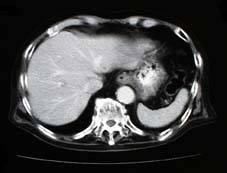

胸腹部の撮影では、呼吸によって臓器が動き画像にズレが生じるため長時間

(20〜30秒)壱岐を止めてもらう場合があります。

腹 部 頭 部 頭 部